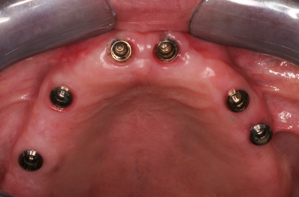

Εμφυτεύματα

Τα οδοντικά εμφυτεύματα ήρθαν για να αλλάξουν τη ζωή μας! Είναι ειδικά σχεδιασμένα για να αποτελούν την υποδομή σε περιπτώσεις αποκατάστασης των δοντιών, για δίνουν την αίσθηση και να έχουν την λειτουργία των φυσιολογικών δοντιών. Αποτελούν μικροσκοπικούς στύλους από τιτάνιο, οι οποίοι εισάγονται στην γνάθο, όπου λείπουν τα δόντια. Τα μεταλλικά τους στηρίγματα λειτουργούν ως υποκατάστατα της ρίζας του δοντιού και τοποθετούνται στη γνάθο μέσω χειρουργικής επέμβασης. Έτσι, ο δεσμός του οστού με το τιτάνιο, δημιουργεί μια ισχυρή υποδομή για τα τεχνητά δόντια, οι ασθενείς χαμογελούν ξανά με αυτοπεποίθηση, ενώ παράλληλα διατηρείτε η δομή του προσώπου τους.

Δείγμα δουλειάς

Μετά